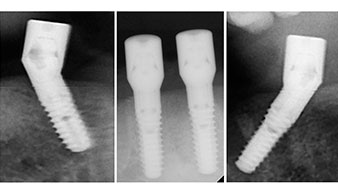

Un CT Scan à faisceaux coniques tridimensionnel (CBCT, Planmeca) a été réalisé au préalable afin de réduire les risques. Il a révélé une qualité et une quantité d'os disponible suffisante pour l'intervention chirurgicale et la restauration immédiate par la méthode All-on-four. En suivant le protocole de ce concept, les implants sont insérés au niveau de 35, 32, 42 et 45 en inclinant les implants distaux jusqu'à 45°, le profil d'émergence se déplace ainsi vers l'arrière et produit un polygone de stabilisation plus large (Fig. 3).

Le protocole chirurgical préconisé pour les implants utilisés (SKY, Bredent Medical) précise une vitesse de rotation de 1.200 tr./min. pour le pré-forage (Fig. 7 - 9).

Ceci correspond à la position suivante prédéfinie dans l'Implantmed. Nous voyons ici le contre-angle W&H tenu à un angle de 45° par rapport à la crête dans la région de 45 afin de préserver le nerf mentonnier. Le trou mentonnier sert de repére anatomique à tous les forages de cette région. Les forages suivants ont été effectués à la vitesse réduite de 300 tr./min. (Fig. 10 et 11).

Une grande stabilité primaire est une exigence essentielle à la restauration immédiate. Pour s'en assurer, le forage n'a pas été taraudé ici. L'unit de chirurgie Implantmed W&H utilisé ici est doté d'un mode spécial adapté qui peut être directement sélectionné et est indispensable à de nombreuses indications. Lors du positionnement des implants, les derniers tours ont été effectués avec une valeur supérieure à 32 Ncm et ont été effectués à la clef à cliquet. Dans un tel cas, nous recommandons d'utiliser la fonction d'auto -taraudage de l'implant et de tourner plusieurs fois les implants vers l'arrière et vers l'avant.

Ceci permet à l'implant de s'approcher de la position finale progressivement sans exercer de pression excessive sur l'os (Fig. 14).

Implants

Fig. 14

La lumière renforce le contraste dans la cavité buccale et améliore la perception visuelle. Le contre-angle et la pièce à main droite S-11 de W&H sont refroidis en externe, ce qui est très avantageux car la solution saline atteint exactement le point visé et peut être ajustée si nécessaire. Les pièces à main et contre-angles droits sont démontables, ce qui est parfait pour respecter les règles d'hygiène et de stérilité. Quatre implants SKY mesurant 4,0 x 14 mm ont été mis en place.